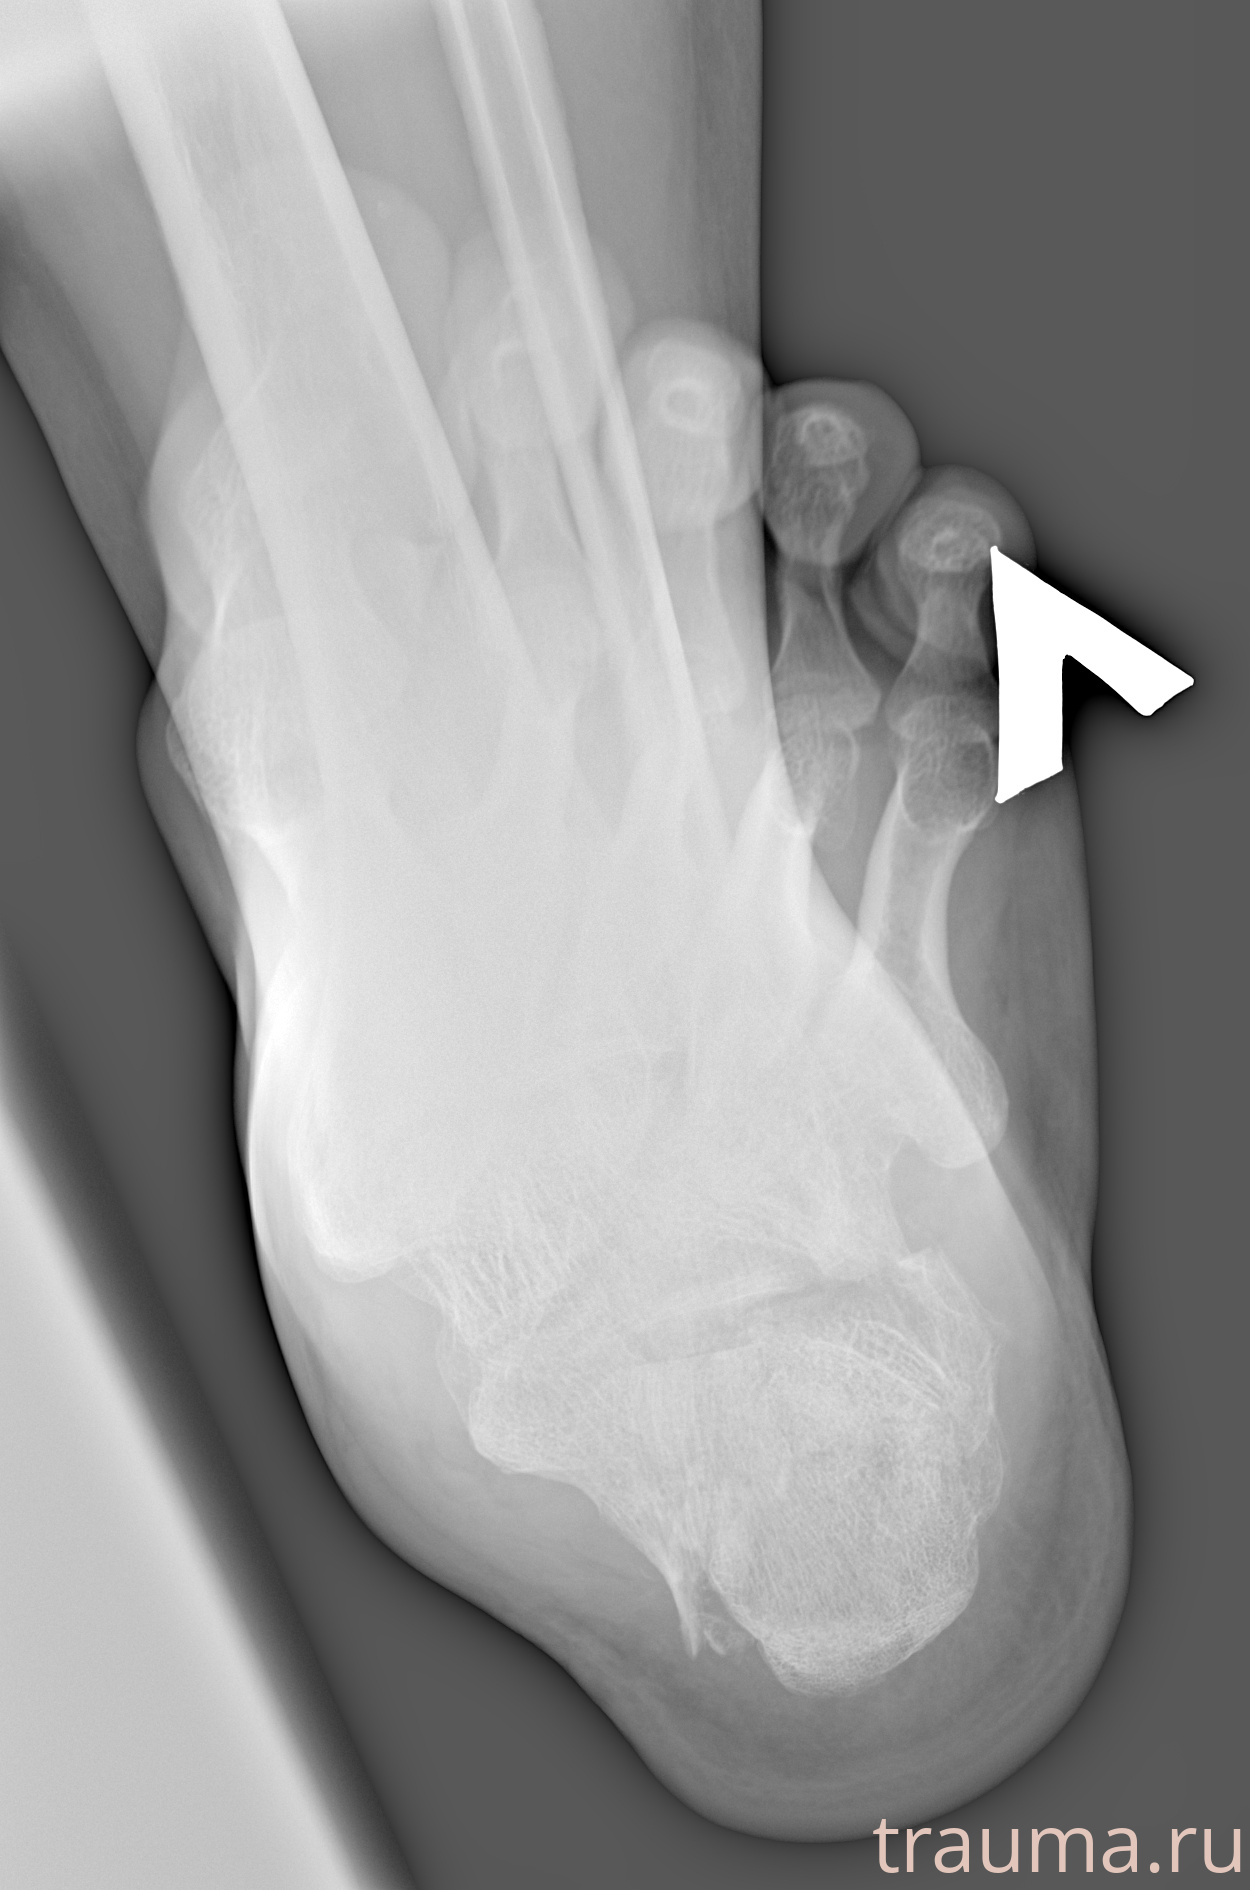

Рентген на дому: по вашему адресу приезжает врач-рентгенолог, травматолог-ортопед с мобильным рентгеновским аппаратом, проводит диагностику травмы или заболевания, делает необходимые рентгенограммы, дает рекомендации по дальнейшему лечению. Получить качественные снимки в домашних условиях возможно благодаря уникальной методике, разработанной МосРентген Центром для института  Склифосовского